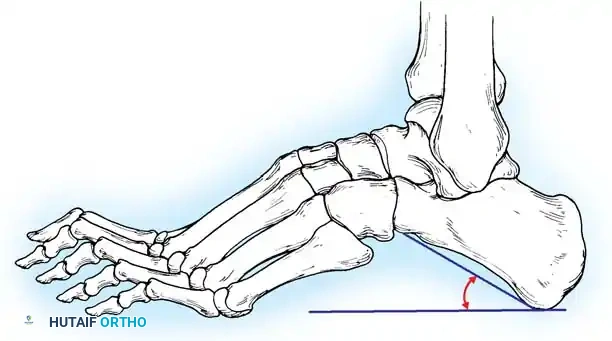

The flexibility of the anatomical components of the cavus foot dictates the surgical algorithm. The Coleman and Chesnut block test is the gold standard for determining the hindfoot-forefoot relationship and assessing whether the hindfoot varus is flexible or fixed.

Technique:

1. The patient stands with the heel and lateral border of the foot on a 1-inch wooden block.

2. The plantarflexed first metatarsal is allowed to hang free off the medial edge of the block.

3. If the hindfoot varus corrects to neutral or valgus, the hindfoot is flexible, and the deformity is entirely driven by the forefoot (the plantarflexed first ray).

4. If the hindfoot remains in varus, the deformity is fixed, necessitating a calcaneal osteotomy or hindfoot arthrodesis.

Fig. 6: Lateral block test. The plantar flexed first metatarsal hangs free; if the supple hindpart of the foot corrects, the varus is forefoot-driven.